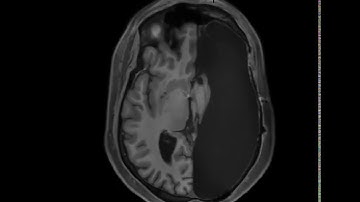

MRI Structural Brain Scan Example